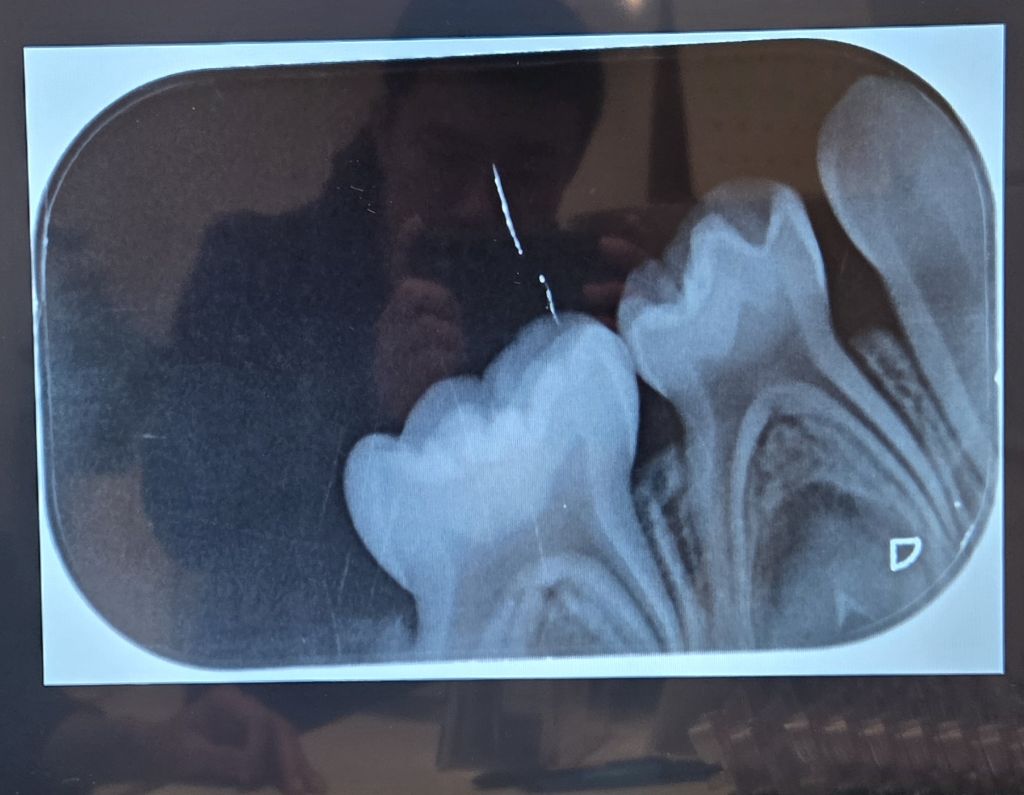

이 치과에서는 모든 어금니에 충치가 다 있으나 (보는 사람 기준) 왼쪽 위에는 매우 약해서 치료를 안 해도 될 수는 있다고 했습니다만 나머지 6개는 모두 치료가 필요하다고 했습니다.

씹는면 충치만 있을 뿐 사이 충치가 없어서

버티는 방법을 실행해 볼 수도 있습니다.

물론 아이들의 씹는면 충치는 빠르게 진행되는 경우가 많습니다.